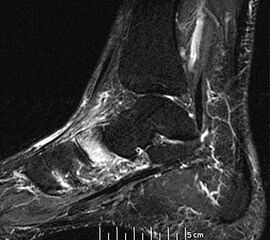

Diagnostische Methode der Wahl ist das MRT, das eine sichere Diagnosestellung erlaubt. Dabei kommt es  im betroffenen Knochen zur signalarmen Darstellung in der T1-Wichtung während T2 gewichtete Darstellungen als Folge des Ödems mit einer  Signalanreicherung in den betroffenen Skelettabschnitten und oft auch in den benachbarten Weichteilen imponieren

10.